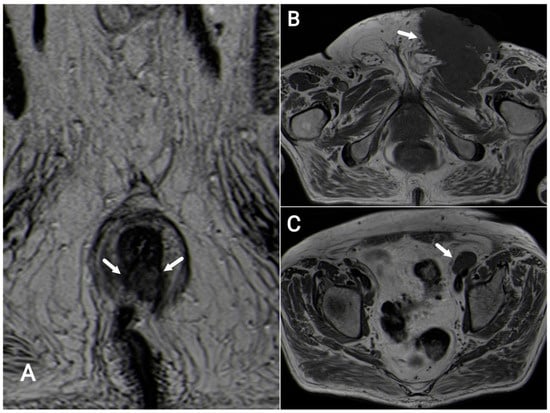

7.1. T-Staging

7.2. N-Staging